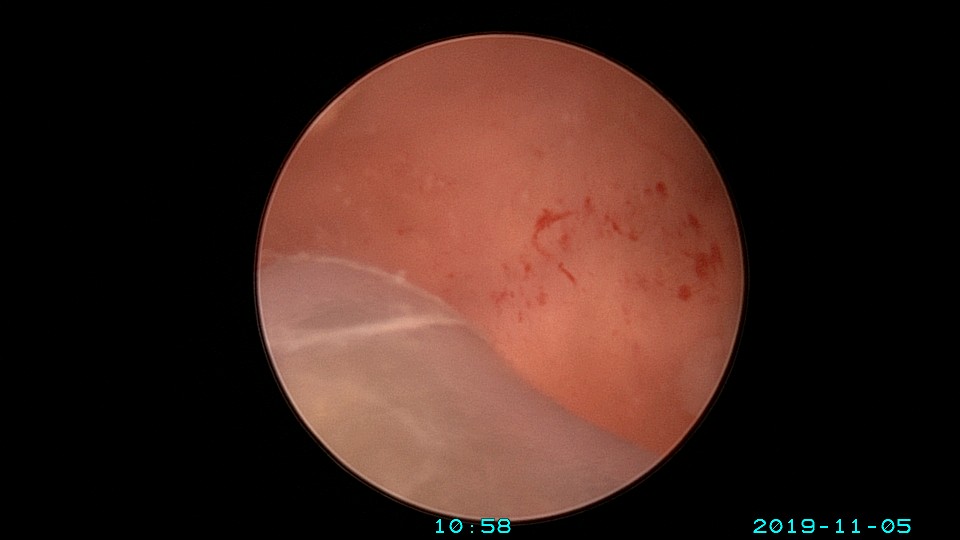

患者26岁,G1P0 ,2019年9月门诊宫腔镜检查发现宫腔重度粘连,2019年10月住院宫腔镜分粘,恢复宫腔形态,显露双侧输卵管开口。2019年11月宫腔镜二探取球囊,宫腔形态正常,双侧输卵管开口可见。2021年3月发现自然妊娠,后因先兆流产、胎心弱在当地医院险些清宫终止妊娠,病人电话咨询我,嘱病人千万不要急着清宫,立即到我院复查,心管搏动良好,住院保胎成功,2021年11月,39周孕剖宫产分娩。2023年7月,再次自然妊娠,39+3周孕剖宫产分娩。现31岁,G3P2。